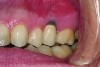

Implant related complications may be classified as minor, intermediate, major reversible/nonreversible, or major nonreversible. For example, a simple complication like a fractured abutment screw is usually considered a minor complication. It usually can be corrected with minimal cost, time, pain, and inconvenience. Treatment may be more involved for an intermediate complication such as a fractured implant (Figure 1). Up the severity scale are major complications, such as when an implant migrates into the sinus2 (Figure 2), or is exposed by mucosa and bone loss and visible to the patient a year after restoration (Figure 3 and Figure 4). Major complications may cause irreversible damage and/or require multiple procedures to try to make the patient “whole,” adding cost, time, pain, and surgeries (Figure 5 and Figure 6), and the patient may or may not receive the original restoration.

A fractured implant is classified as an intermediate complication

Figure 1